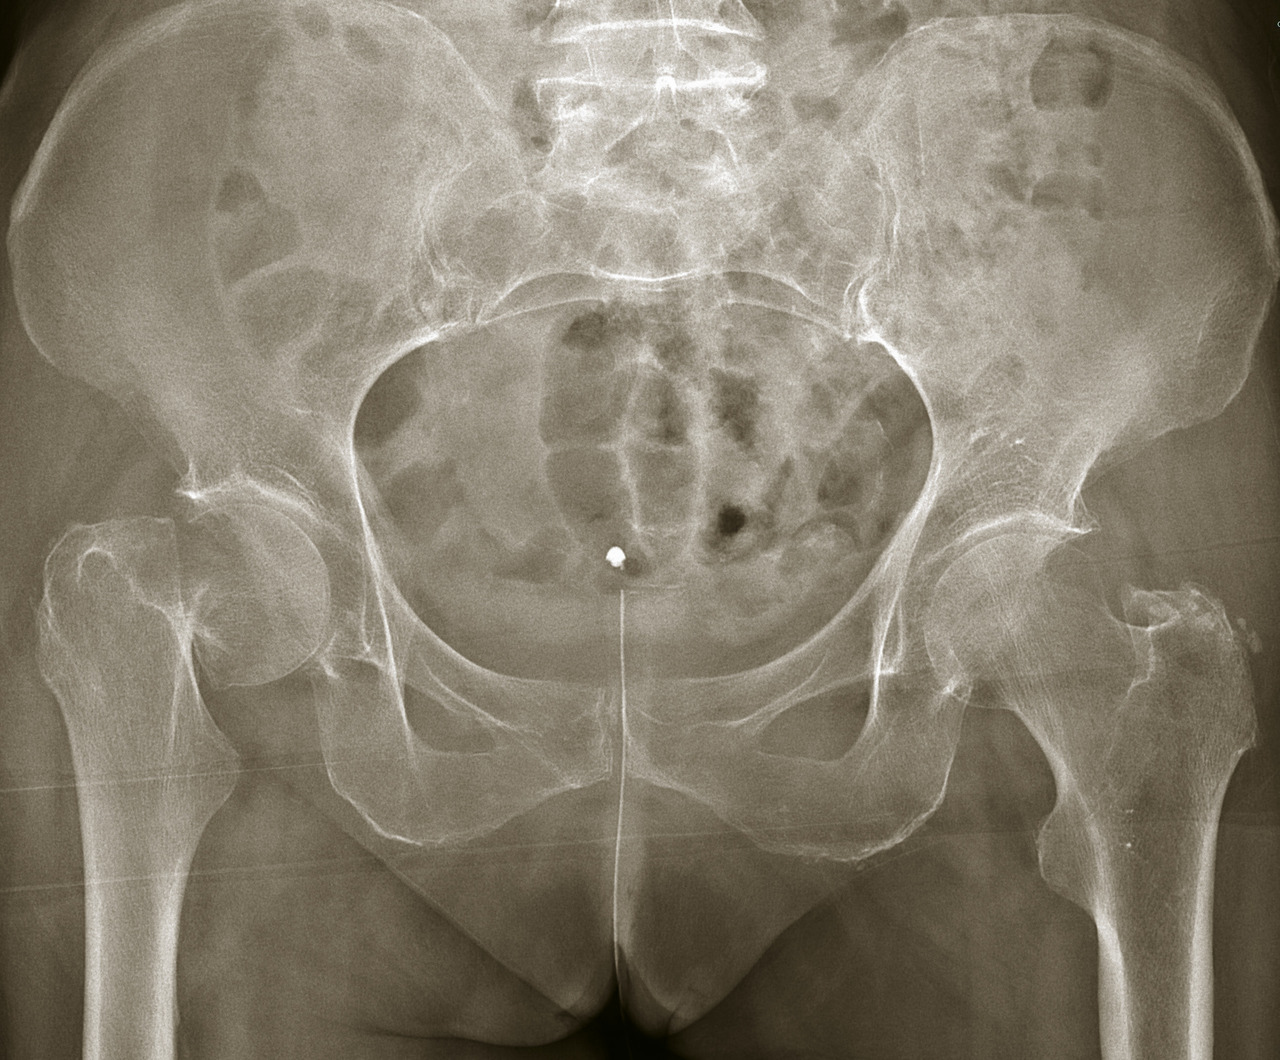

Si, à la lecture de la radiographie, il n’y a pas de fracture évidente au niveau de l’extrémité supérieure du fémur, il faut bien regarder au niveau des branches ilio- et ischiopubiennes, dont la fracture constitue le principal diagnostic différentiel clinique. Il faut également s’assurer qu’il n’y ait pas de fracture habituellement peu déplacée du cotyle. En l’absence de telle fracture avec néanmoins une symptomatologie caractéristique, il faut poursuivre les investigations. L’IRM serait a priori le meilleur examen, mais son accès n’est pas toujours facile en urgence, et un bon nombre de patients sont porteurs de pacemaker, qui contre-indique formellement cet examen. Il est donc réalisé en général un scanner, au mieux associé à une scintigraphie. C’est ce qui permet de faire le diagnostic des fractures occultes.

Les fractures pathologiques ne sont pas rares au niveau de l’extrémité supérieure du fémur. Il faut toujours analyser rigoureusement la trame osseuse, à la recherche d’ostéolyse ou d’image anormale. Il faut également rechercher de telles images sur le reste du fémur et sur le bassin, constituant alors un argument de plus en faveur d’une fracture sur métastase.